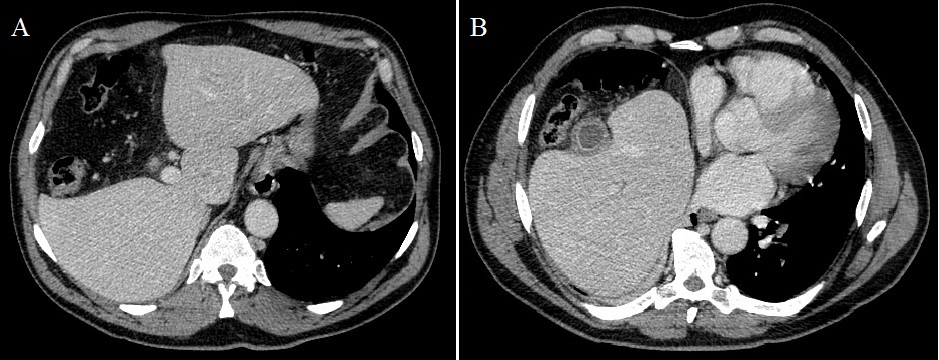

Acalculous cholecystitis in patient with hepatic hypogenesis and chilaiditi sign

A 66-year-old male patient was admitted in our outside hospital’s emergency room after 4 days of epigastric pain, nausea and vomiting. No fever, dysthermia or respiratory symptoms were related. The pain irradiated to right hypochondria and even to right chest. Laboratory tests showed slight elevation of liver enzymes and leukocytosis. Abdominal CT revealed hepatodiaphragmatic colonic interposition, segmental agenesis of the right hepatic lobe (A) and a gallbladder with thickened walls and inflammatory changes without any stone (B). The patient did well with antibiotic treatment and was discharged home. Hepatodiaphragmatic interposition of the intestine, known as Chilaiditi sign or syndrome, was first described by Demetrius Chilaiditi in 1910, with an incidence of 0.025-0.28%. Predisposing factors include absence of the normal suspensory ligaments of the transverse colon, redundant colon, right hemidiaphragm elevation, atrophy or hypogenesis of the right hepatic lobe, etc. Agenesis or hypogenesis of the right liver lobe is an extremely rare congenital anomaly and one of the rare causes of Chilaiditi sign or syndrome. It is considered to be caused by a failure of the right portal vein to develop, or an error of mutual induction between the primitive diaphragm and the endodermal diverticulum representing the primitive liver. The differential diagnoses of Chilaiditi syndrome include pneumoperitoneum, diaphragmatic hernia, subdiaphragmatic abscess, bowel obstruction and volvulus. No chirurgic intervention is required for a patient with Chilaiditi sign, they respond to medical management, and surgery is reserved for those who do not respond to usual conservative line of management.